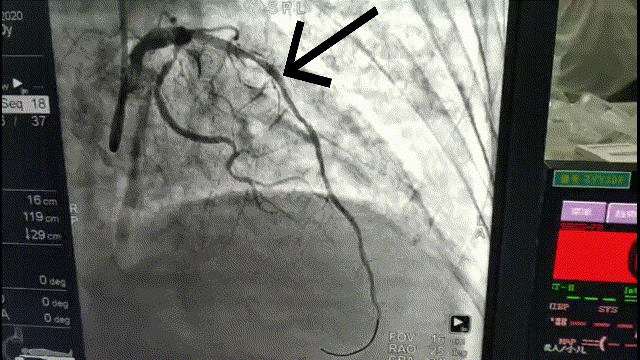

张大娘听从医生建议佩戴动态心电图检查,结果显示:窦性心律,窦性停搏,交界性逸搏心律,大于2.5秒的停搏有71次,最长停搏时间为5.36秒,房早283个,成对房早30次,房速10次。